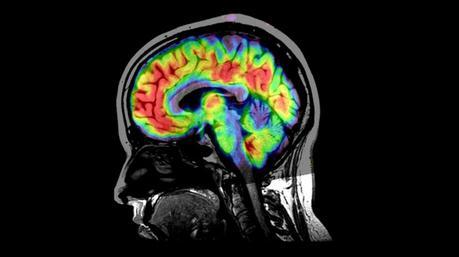

Al final, el efecto fisiológico no es más que una consecuencia que el efecto placebo que tiene sobre el cerebro. La gran mayoría de la información que tenemos sobre los placebos y el cerebro proviene del estudio del dolor. Lo que se ha observado, hasta la fecha, es que el dolor puede ser manipulado para reducirlo con sustancias placebo. Al observar el cerebro con neuroimagen lo que apreciamos es que el efecto placebo tiende a desactivar en parte los centros dedicados a sentir e interpretar el dolor: el tálamo, la corteza somato-sensorial y la ínsula, entre otros. Cuanto más largo es el tratamiento, más se acomodan estas zonas y menos dolor siente el paciente.

Además, el tratamiento con los placebos, según se ha comprobado, también es capaz de disparar una respuesta que viaja a través de la médula espinal, actuando sobre un tejido especial (el tejido gris periacueductal) que produce sustancias naturales que reducen el dolor. Esto último es muy importante y se ha comprobado que bloquear a esta sustancia reduce el efecto placebo por lo que esta sustancia gris periacueductal es un componente principal en el efecto. Otros puntos en el que actúa el efecto placebo son el córtex prefrontal y la amígdala, provocando una mayor regulación de opiáceos naturales en todo el cuerpo. Por otro lado, la amígdala , que controla el estado de ansiedad, por ejemplo, parece muy afectada por el efecto placebo. Estos son solo algunos pequeños ejemplos, porque lo que se observa es que el efecto placebo afecta a cada una de las partes del cerebro con una intensidad inesperada.